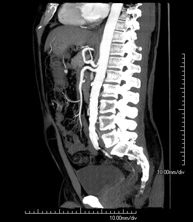

- Abdominal aorta CT angiography

A non-invasive diagnostic test that involves studying the abdominal aorta by obtaining high-definition anatomical images using CT (computed tomography) equipment and iodinated contrast. With the aid of workstations specialised for arterial studies, the image quality supports 2D and 3D reconstructions. It is indicated in patients with vascular disease (atherosclerosis), aortic aneurysms, abdominal pain of possible vascular origin, pre-surgical studies of lesions adjacent to the abdominal aorta as a vascular ‘map’, etc. Information obtained non-invasively is indispensable for patients requiring percutaneous or surgical processing. In patients who only require tracking of vascular lesions, this technique is the non-invasive technique of choice, together with MRI angiography.

- Aortoiliac CT angiography

A non-invasive diagnostic test that involves examining the iliac arteries and abdominal aorta, obtaining high-definition anatomical images using CT (computed tomography) equipment and iodinated contrast dye. With the aid of workstations specialised for arterial studies, the image quality supports 2D and 3D reconstructions. This test is particularly recommended as a pre-surgical study (vascular map) prior to percutaneous or surgical interventions on the abdominal aorta, as a complementary study in patients with lower limb ischaemia, etc.